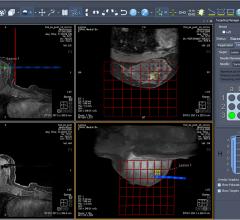

July 11, 2017 — Volpara Solutions Inc. will showcase its new Volpara Enterprise DDP software at the Association for ...

May 30, 2017 — Kubtec announced recently that the U.S. Patent Office has granted the company an additional patent for ...